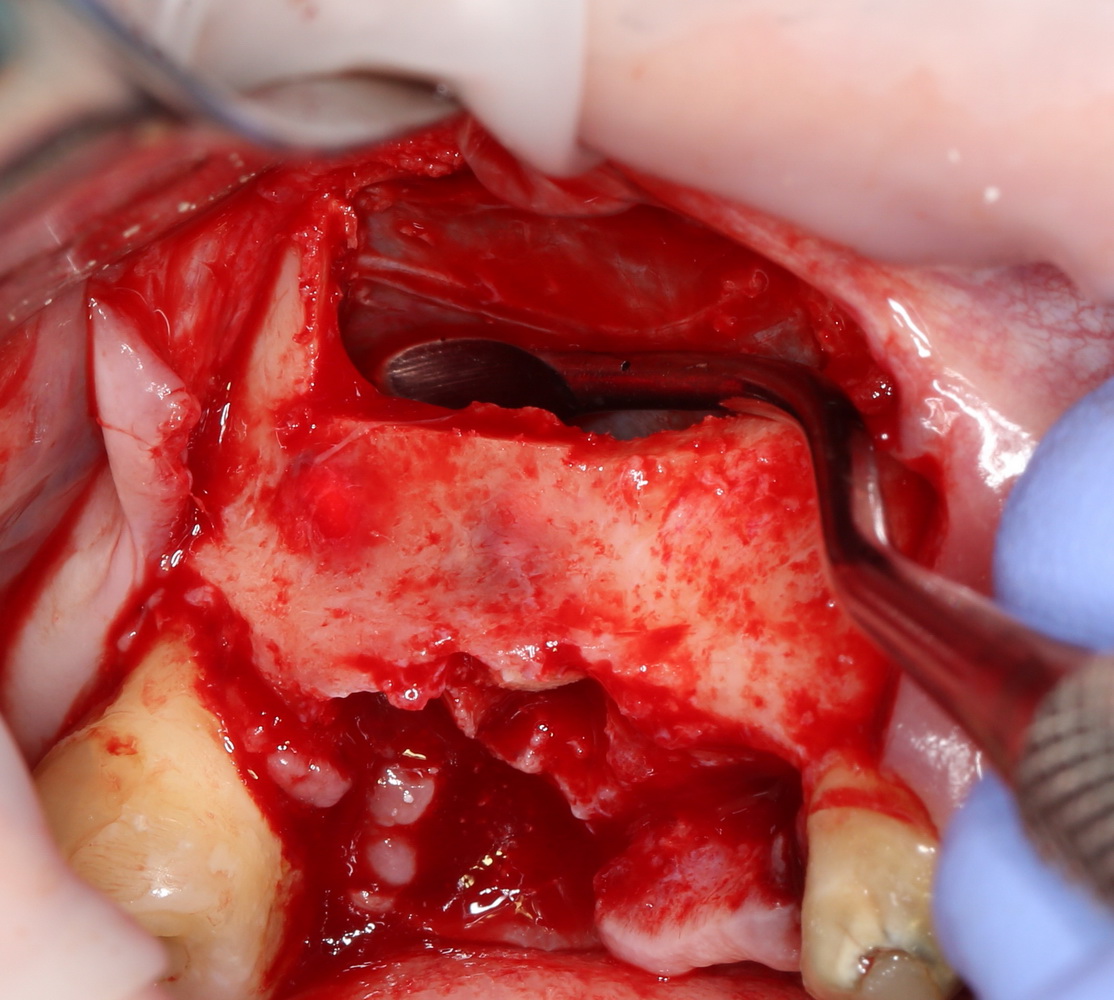

Скелетирование стенки верхней челюсти – следующий этап хирургического вмешательства. Производится он с помощью распатора. При этом, следует соблюдать особую осторожность, особенно при тонкой слизистой оболочке – в противном случае, ее можно легко повредить (рис 21, 22).

Рисунок 21, 22. Разрез слизистой оболочки и скелетирование стенки верхней челюсти

По рисункам видно, что даже при относительно небольшой длине разреза можно получить хороший обзор операционного поля.